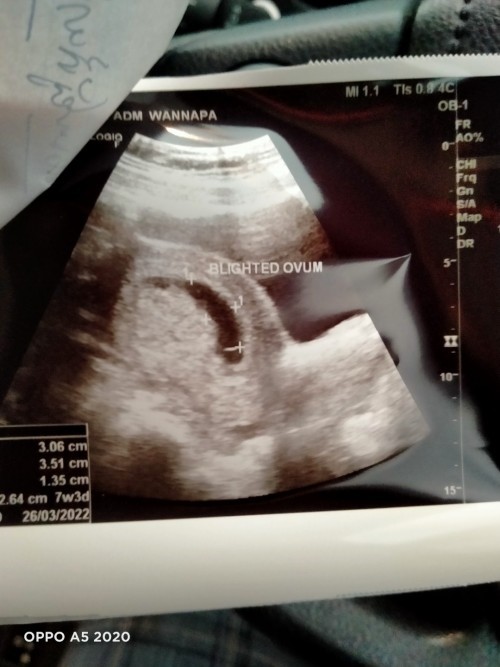

ท้องลมหรือไม่

วันนี้ได้เข้าไปอัลตร้าซาวกับหมอสูติได้พบว่ามีถุงตั้งครรภ์แต่ไม่มีตัวอ่อน ถ้านับอายุครรภ์จากปจด.คือ10w.แต่คุณหมอบวกลบท้องลม คุณแม่นัดอีก2อาทิตย์ถ้าไม่เจอตัวอ่อนก็เปนท้องลม หมอบอกอายุครรภ์อาจจะพึ่งได้7w ใครเจอแบบนี้บ้างมั้ยค่ะ เครียดยุค่ะ

หมอคอนเฟิร์มแล้วว่าท้องลม ขอบคุณสำหรับความคิดเห็นจากทุกๆคนค่ะ😥